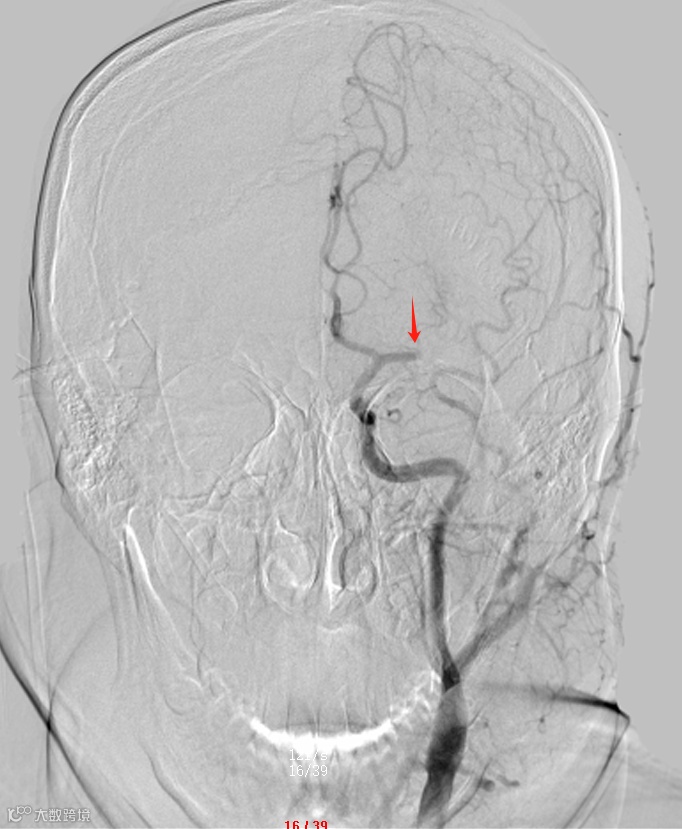

术前,左侧大脑中动脉闭塞